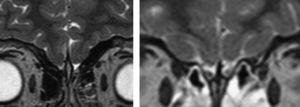

Caso 1: varón de 16 años que consulta por hipogenitalismo. Los antecedentes familiares son desconocidos. Entre los antecedentes personales, destaca que a los 14 años se le diagnosticó e intervino de una hernia diafragmática izquierda que contenía la cámara gástrica, el bazo y el colon descendente en la cavidad torácica. Refería anosmia desde la infancia. En la exploración se observa peso de 44,2kg (percentil [P]3), talla de 155cm (P10). Los genitales son masculinos con micropene (pene de 2 × 1cm) y criptorquidia bilateral (testes inguinales de 1 cc, que se pueden descender al escroto). Presenta estadio i de Tanner. En las pruebas complementarias se observa cariotipo 46XY; testosterona total (T) de 0,1ng/ml (valor normal [VN]: 2,7¿8,3); test de Gn-RH (100¿g intravenosa [i.v.]: 0¿, 20¿, 60¿); FSH (follicle-stimulating hormone 'hormona foliculoestimulante o folitropina') inferior a 1,0; 2,1; 3,7mU/ml; LH (luteinizing hormone 'hormona luteinizante o lutoestimulante') inferior a 1,0; 2,7; 3,4mU/ml. El resto de la función adenohipofisaria se presenta sin alteraciones. La edad ósea es de 12 años (según el atlas de Greulich y Pyle). La resonancia magnética (RM) muestra aplasia de bulbos olfatorios (figura 1). Se realiza orquidopexia bilateral y se inicia tratamiento con gonadotropina coriónica humana (HCG) (1.000 U semanales) que el paciente rechaza a la tercera dosis, por lo que se sustituye por enantato de testosterona, inicialmente a una dosis de 50mg cada 3 meses y progresivamente se aumentó hasta llegar al mantenimiento con 100mg mensuales. Actualmente tiene un estadio IV de Tanner, con pene de tamaño normal y testes de 4 cc.

Figura 1. A la izquierda, resonancia magnética (RM) con ausencia de bulbos olfatorios; a la derecha, RM normal.